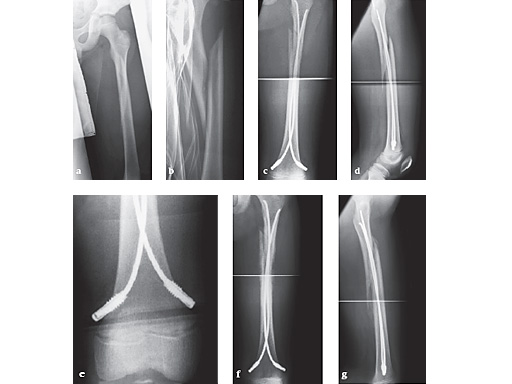

12-year-old boy; snow-board injury long spiral proximal femoral fracture (32D/5.1) primary indication for operation with ESIN and End Cap.

ab

Injury x-rays.

cd

Postoperative x-rays show a correct alignment and length. Fixation with 3.5 mm TEN and End Caps was performed.

e

This detail view shows the correct positioning of the End Caps.

fg

4 1/2 weeks postoperative a good callus and correct alignment was visible, full weight bearing was allowed.